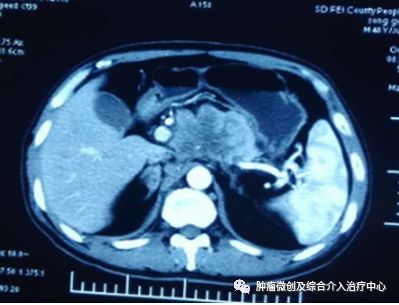

胰腺肿瘤穿刺活检CT